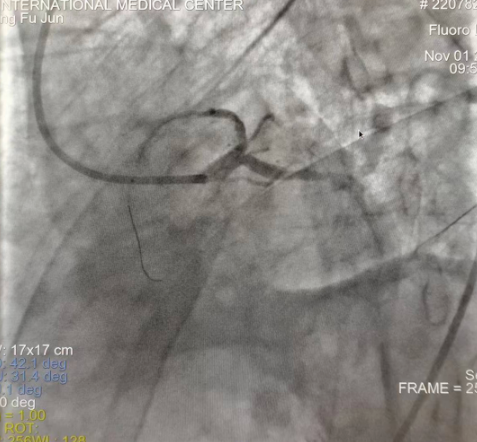

閉塞的血管再通時(shí)間取決于急救時(shí)長(zhǎng)、轉(zhuǎn)運(yùn)時(shí)長(zhǎng)和治療時(shí)長(zhǎng),在前兩方面,醫(yī)院已為患者爭(zhēng)取了最短時(shí)間?;颊呒覍龠h(yuǎn)在陜北,雖然已在趕來(lái)的路上,但最快抵達(dá)西安也要3小時(shí),在與患者家屬電話溝通同意急診手術(shù)后,醫(yī)療總值班代家屬簽字,康曉軍在請(qǐng)示心臟病醫(yī)院王海昌院長(zhǎng)及心臟內(nèi)科CCU尚福軍主任后,積極進(jìn)行術(shù)前準(zhǔn)備。在沒有家屬陪同、沒有交費(fèi)、沒有辦入院手續(xù)的情況下,患者經(jīng)胸痛中心綠色通道被送往心臟冠脈介入手術(shù)室,打通了完全閉塞的心臟前降支近段血管。